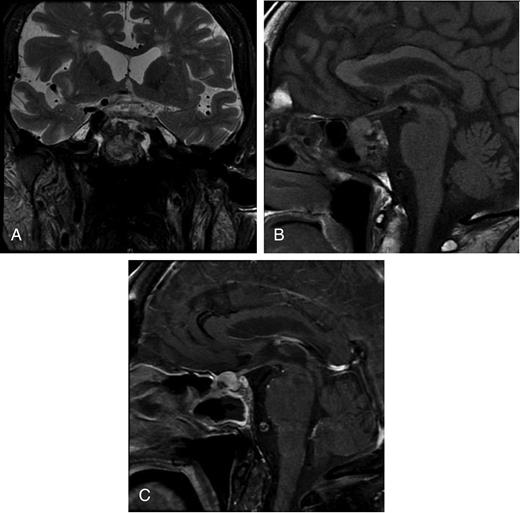

MRI performed 3 weeks after initial presentation. (A) T2-weighted MRI coronal section displaying an expanding, infiltrative pituitary fossa mass. (B) T1-weighted MRI sagittal view, indicating that the lesion is locally infiltrating the sphenoidal sinus. (C) Post-gadolinium sagittal T1-weighted MRI indicating a heterogeneously enhancing mass.

The patient's headache worsened despite management with simple analgesia. A repeat MRI performed 3 weeks after presentation demonstrated that the lesion had expanded in size and appeared to be breaching the diaphragma sella, with extension to the inferior surface of the optic chiasm (Fig. 2).